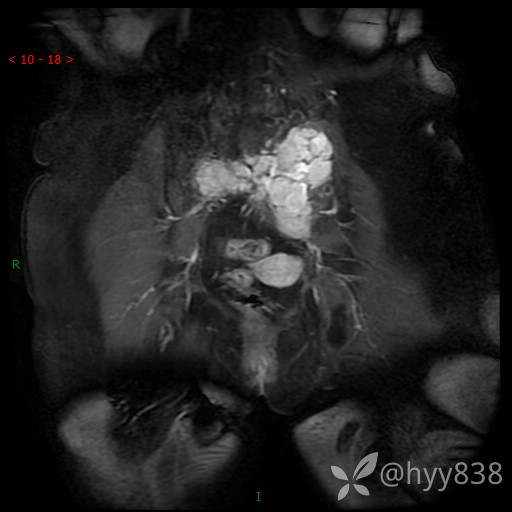

老年女性,腰痛不适就诊。少见病例,信号特征或许是一丝线索,请分析--结果公布~

简要病史:腰部疼痛不适,当地人民医院CT示骶骨骨质破坏并髂骨累及

骨盆MRI平扫(T1WI+T2WI+DWI)(外院CT,不能上传)

CE